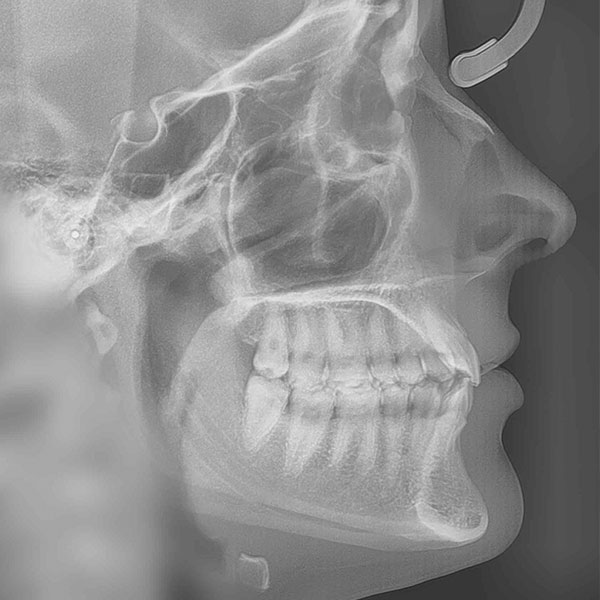

Unsere Leistungen für Ihr Lächeln

Unser freundliches und kompetentes Praxisteam hält für Sie das gesamte Leistungsspektrum für Ihre optimale kieferorthopädische Behandlung bereit. Wir beraten - Sie entscheiden.

Kieferorthopädie für Kinder und Jugendliche

Erwachsenen- Behandlungen

Frühbehandlungen

Unsichtbare Zahnspangen

Kieferorthopädisch- kieferchirurgische Kombinationsbehandlungen

Ganzheitliche Funktionskieferorthopädie